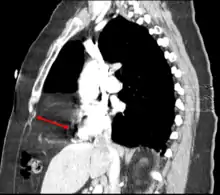

| Morgagni hernia seen on a chest radiograph. | |

Morgagni hernia

This rare anterior defect of the diaphragm is variably referred to as a Morgagni, retrosternal, or parasternal hernia. Accounting for approximately 2% of all CDH cases, it is characterized by herniation through the foramina of Morgagni which are located immediately adjacent and posterior to the xiphoid process of the sternum.[4]